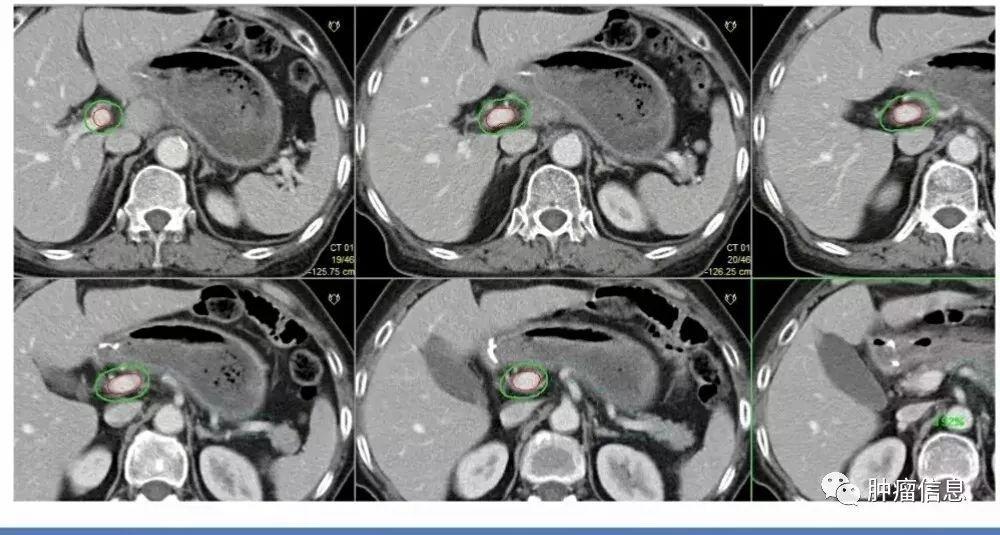

髂总淋巴结

从腹主动脉分叉到髂内动脉的分支之间的髂总血管周围淋巴结。上界:主动脉分叉或腰4-5间隙下界:髂总动脉分叉前界:动静脉前7mm后界:L5椎体和骶岬(包括腰大肌与椎体旁间隙)外侧界:动静脉旁7mm(腰大肌)勾画时应包括血管及周围7mm区域,(包括骨、肌肉、小肠),以及所有可疑淋巴结、淋巴囊肿、手术银夹。

髂内淋巴结

髂内动静脉周围淋巴结上界:髂总分叉下界:尾骨肌上缘或坐骨棘其他边界具体范围见下图所示:

髂外淋巴结

上界:髂总分叉下界:股骨头上缘其他边界见下图: